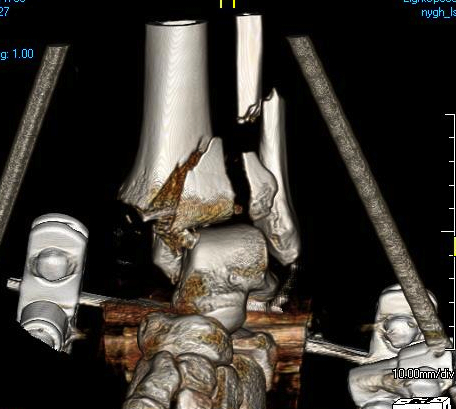

Technique of ankle bridging delta frame

- two pins in the tibia away from surgical site

- transcalcaneal threaded pin placed medial to lateral

- pin in base of first metatarsal to keep foot in neutral position and prevent equinus contracture

- note: pin in base of first metatarsal places deep plantar branch of dorsalis pedis at risk

+/- fibular fixation

- can keep fracture out to length / maintain reduction

- must avoid fibula malreduction as makes later tibial ORIF very difficult

- must consider future incisions

- should only be done by definitive surgeon

- best through posterolateral approach

CT after external fixation application